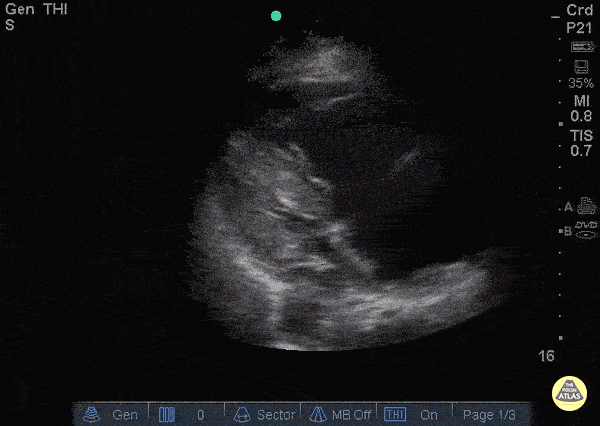

Right Ventricular Dysfunction - Right Heart Thrombus pre TPA

88 y/o F presenting with chest pain and syncope. Shortly after arrival patient went into brief period of cardiac arrest with ROSC. POCUS shows massive thrombus floating back and forth across the tricuspid valve with a dilated right ventricle, D-sign, and global right heart hypokinesis. Patient was given TPA bolus. Approximately 1 hour after pushing TPA, repeat POCUS with resolution of thrombus on RV, but patient continued RV hypokinesis. Patient vitals stabilized enough for a CTA which showed left main pulmonary artery extending into both left upper lobe and left lower lobe branches with evidence for right heart strain. Dr. Roderick Alfonso, Maan Al Dubayan, Andrew Sweeny - Kings County Emergency Medicine